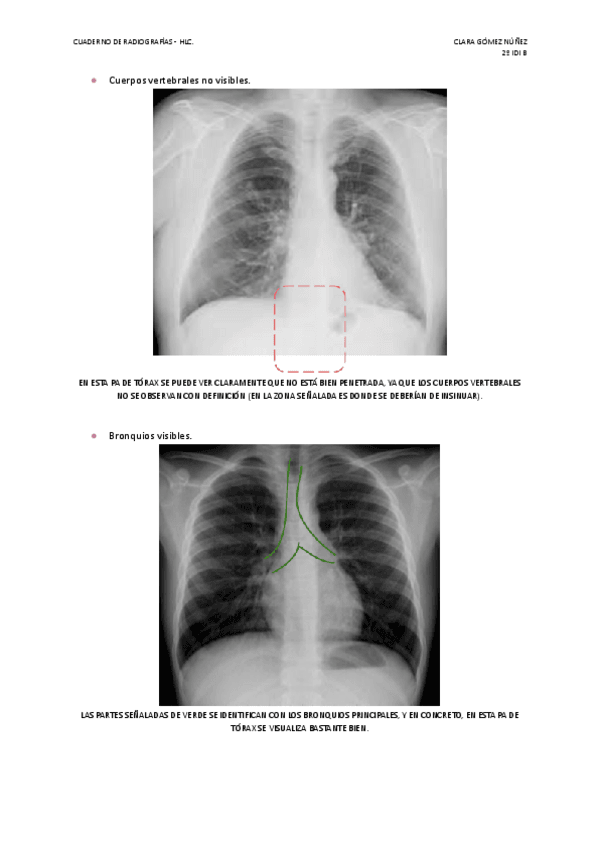

He publicado nuevos apuntes de Técnicas de Radiología Simple: Cuaderno-de-fotos-radiograficas.pdf

14 páginas